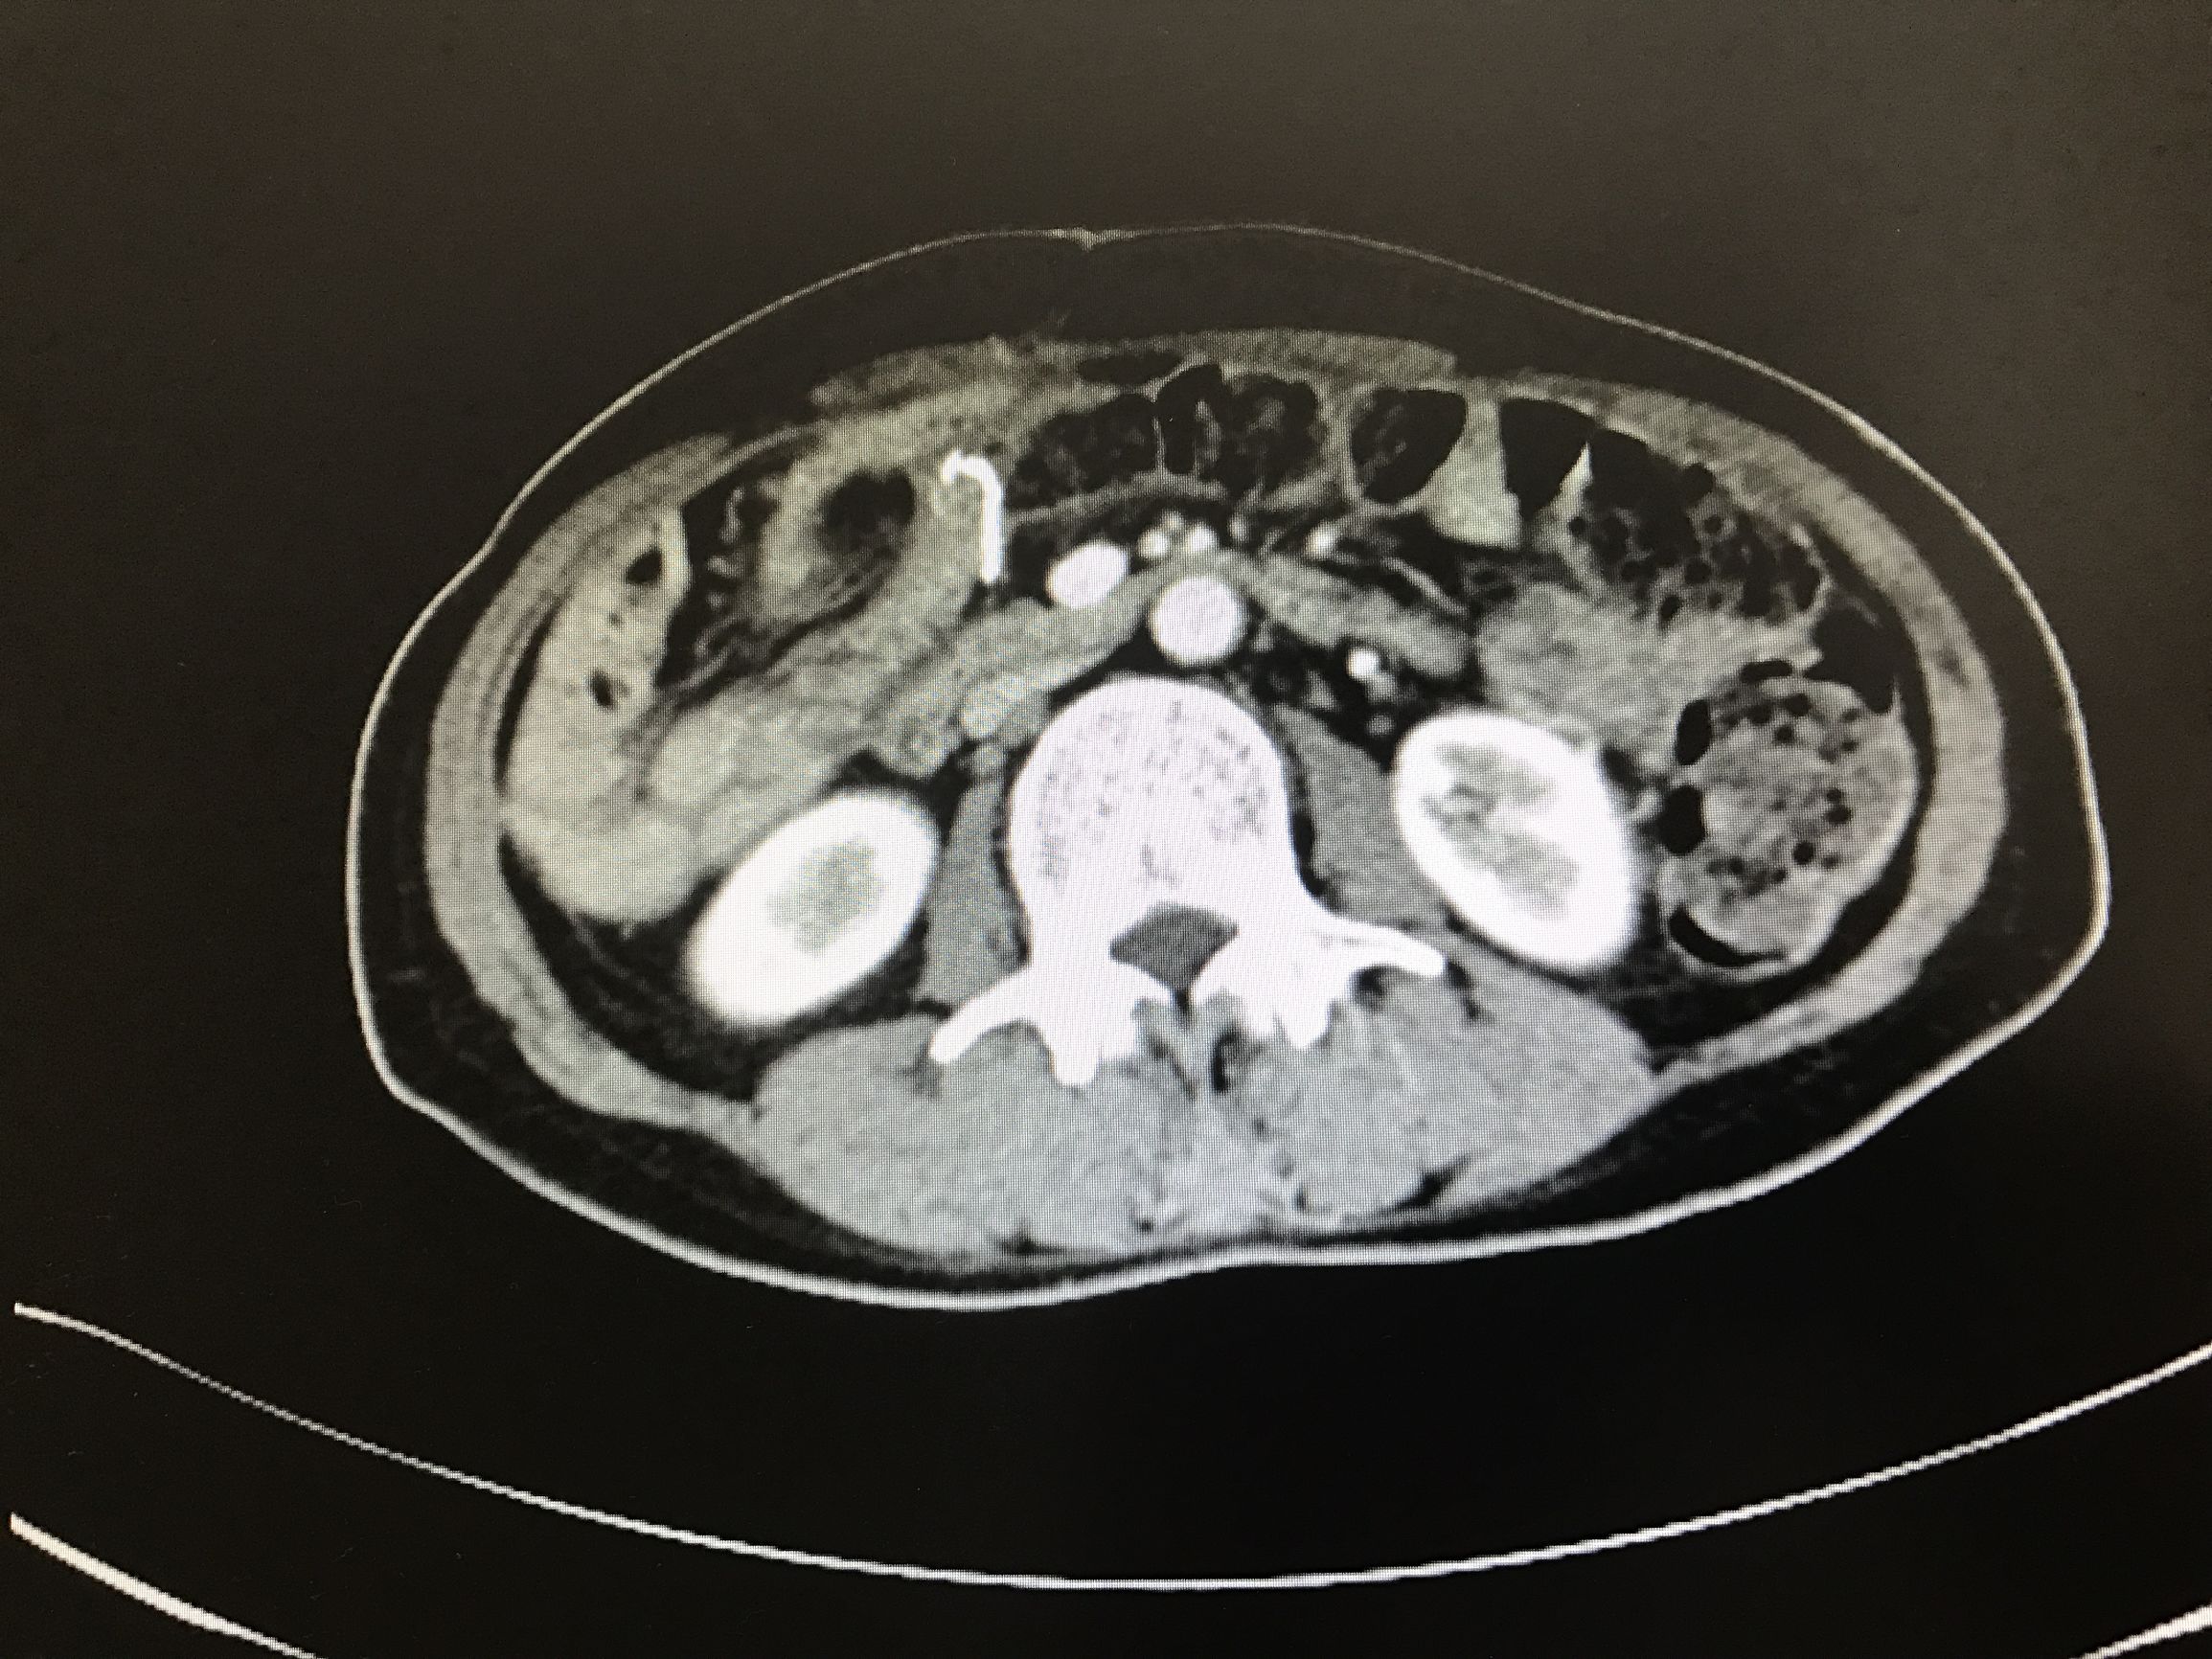

因为患者有下腹胀痛的感觉,所以被分诊到了妇产科。妇产科做了阴道后穹窿穿刺,结果很糟糕:浸润性粘液腺癌!

后来经过一系列的检查被确诊为阑尾黏液腺癌!

阑尾黏液腺癌一般在早期没有任何症状,等到出现腹痛等症状时为时已晚。因为只有它已经侵及腹膜腔,广泛种植在腹盆腔脏器以及大小网膜表面,黏连形成肿块或者形成大量黏液性积液,这个时候患者才会出现一系列症状。